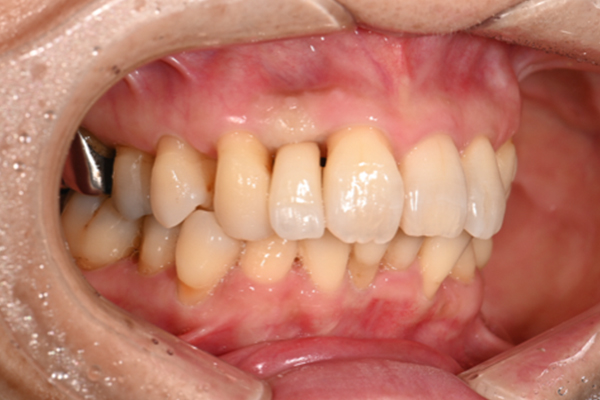

| 主訴 | 奥歯で噛めない、顎が痛い |

|---|---|

| 治療内容 | 奥歯のインプラント治療、前歯・奥歯の被せ物治療 |

| 治療期間 | 6ヶ月 |

| 治療費 | 350万円 |

| 治療リスク | 被せ物をつけた初期の段階で歯がしみることがある(時間とともに改善する) インプラント治療後に3日程度痛みと腫れを伴うことがある |